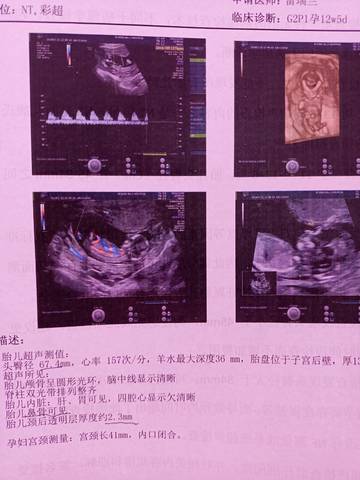

昨天做的Nt出于好奇,大家能帮我看看是男孩还是女孩

树友7x0lk6 2021-12-10 16:35